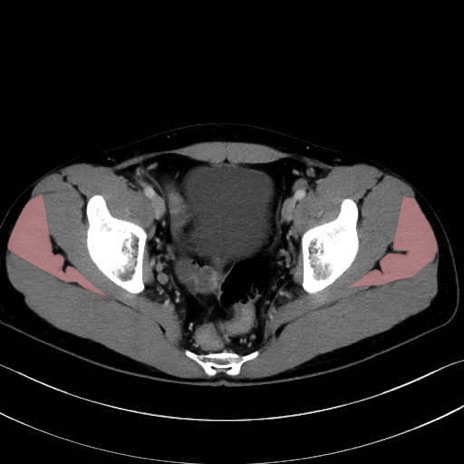

中殿筋 (Gluteus medius)

大腿筋膜張筋 (Tensor fasciae latae)